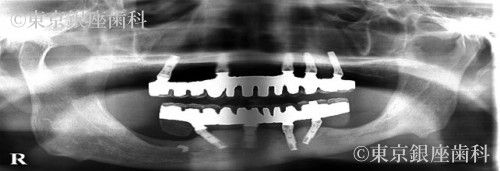

After

ブレードインプラントが下顎管に近接しているので、インプラント除去による下顎の知覚麻痺が生じるリスクを術前のCTの分析で診査し、リスクを避けました。また骨造成は行わず、既存骨(ご本人様の骨)イへのンプラント埋入を行いました。上顎は5本のインプラント、下顎は4本のインプラントを支えとした、上下顎への全顎的な人工歯を装着することで口腔機能の回復が得られた症例となりました。患者様にとても満足の得られることができた症例です